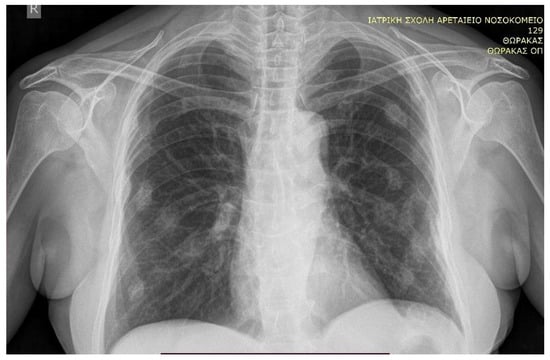

The patient was then referred to the surgical department for left adrenalectomy due to adrenal CS. As part of her preoperative assessment, she had a chest X-ray (Figure 3) where multiple round-shaped nodular opacities were accidentally discovered. The subsequent chest computerized tomography (CT) confirmed these as old porotic costal fractures (Figure 4), excluding any suspicion of an infection or metastasis [10,11,12].

Figure 3. Chest radiograph (posteroanterior view) obtained pre-operatively with bilateral nodular opacities reminiscent of metastatic disease.